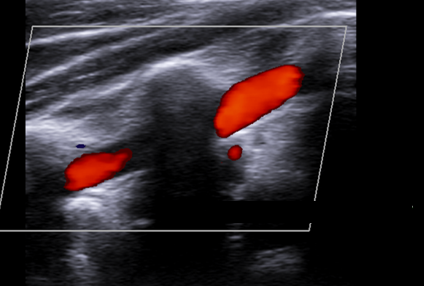

What pathology is being shown in this image?

Stenosis